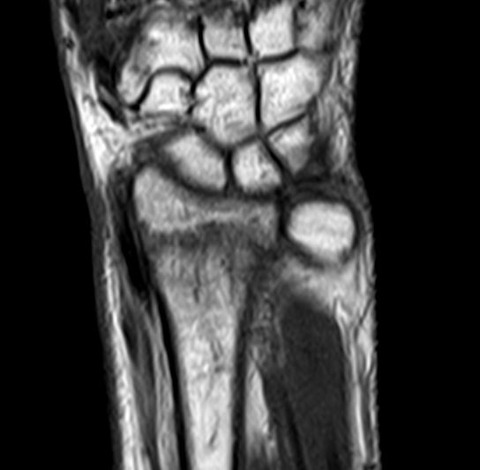

念のためにMRIを撮像すると、やはり橈骨遠位端骨折のようです。圧痛点も関節ではなく、橈骨遠位端なので、画像と身体所見が一致しました。

それにしても非荷重肢である橈骨遠位端に不顕性骨折というものが存在するのか? 医中誌で検索すると、数は少ないものの、ある程度まとまった報告がありました。

なるほど、小児と高齢者では機転が異なるようですが、非荷重肢であるものの橈骨遠位端にも不顕性骨折は存在するようです。いや~勉強になりました。